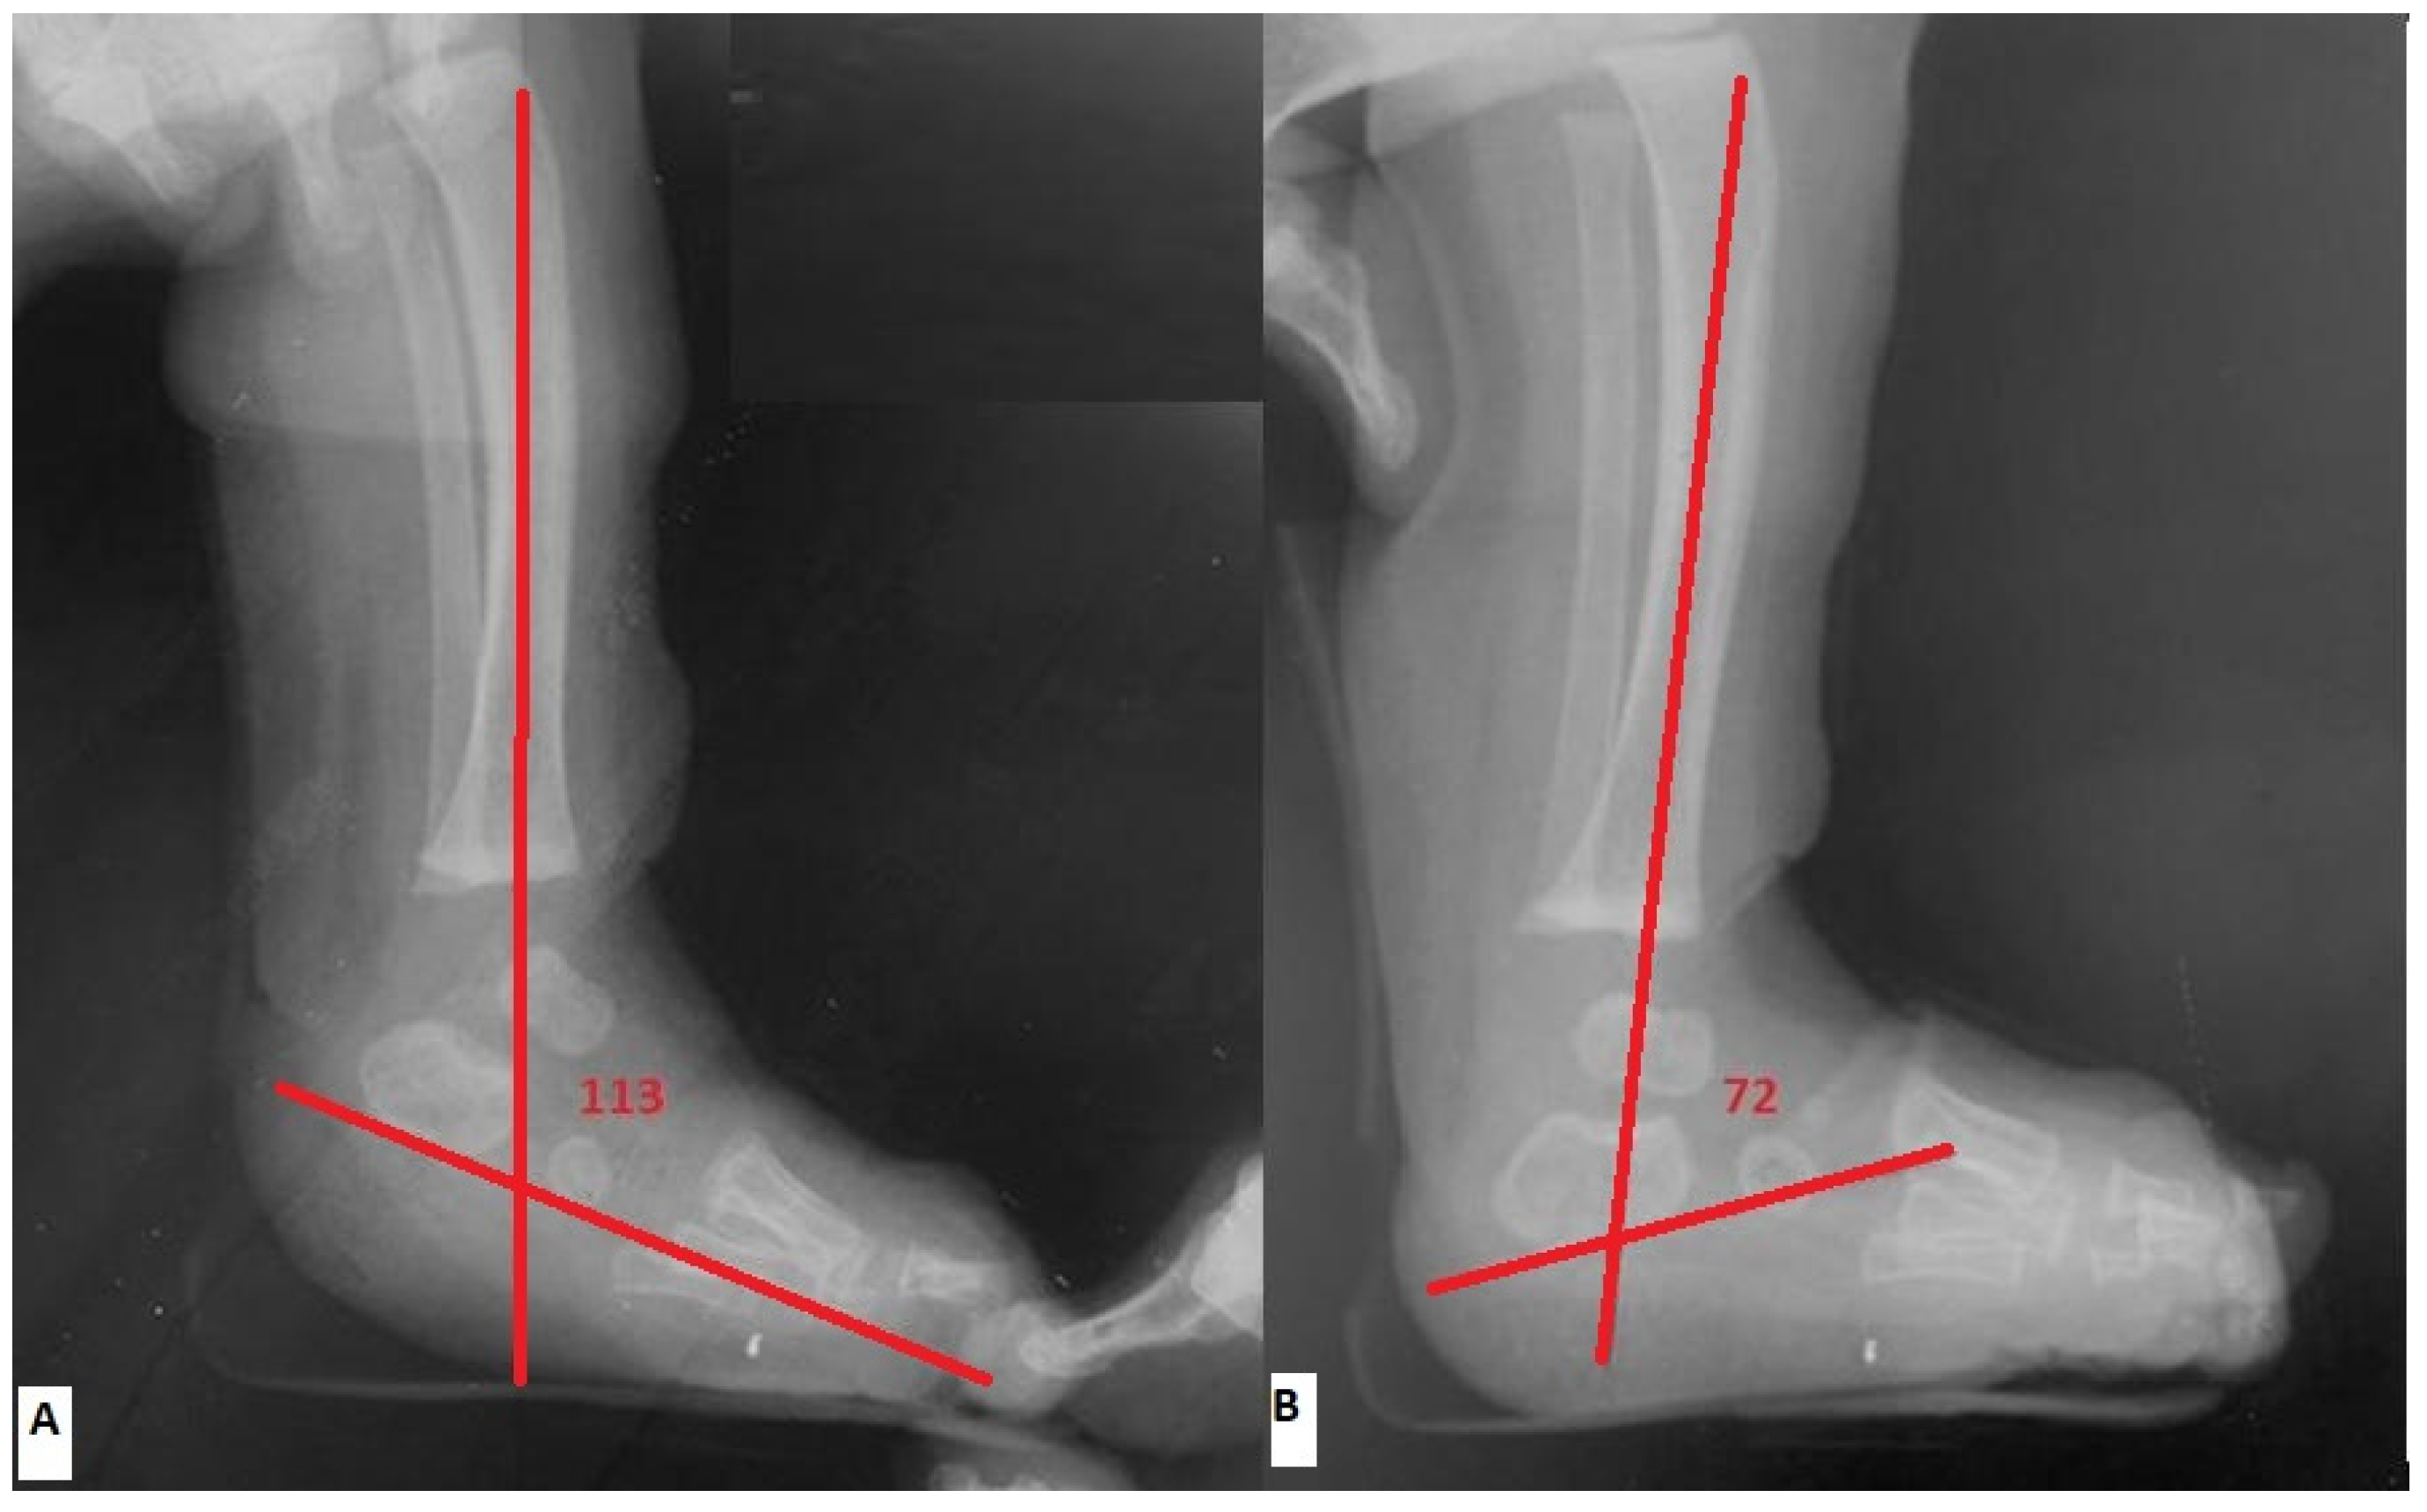

Radiographic evaluation was made pre-operatively (within 4 days prior to tenotomy) and post-operatively (within 7 days right after the final cast removal) by assessing the lateral tibio-calcaneal (TibC) angle on true lateral radiographs, as depicted in Figure 2. The lateral TibC angle was measured based on the angle formed by the intersection of a line drawn through the longitudinal axis of the tibia and a line drawn through the long axis of the calcaneus [3,14,15]. In cases where the tangent of the bottom edge of the calcaneus nucleus was uncertain, the long axis of the ossific nucleus was used as a reference.

Figure 2. Radiographic evaluation by assessing the lateral tibio-calcaneal (TibC) angle on true lateral radiographs. (A) pre-operatively (B) post-operatively.